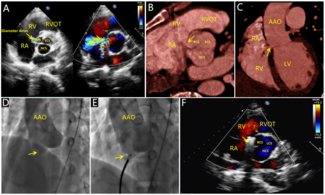

A 31-year-old man presented to our cardiac center with progressive dyspnea and fatigue. Physical examination revealed a continuous 3/6 systolic murmur at the lower left sternal border.